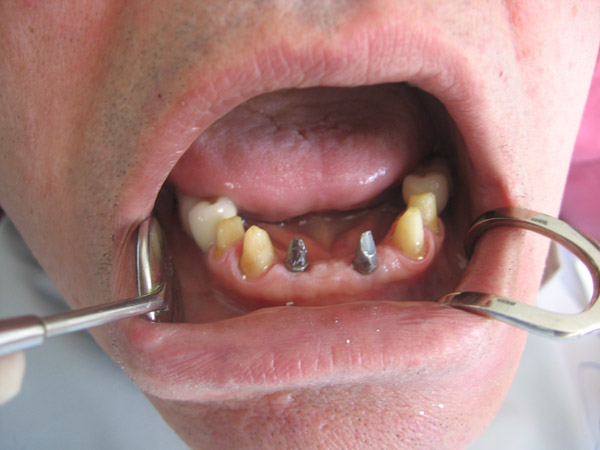

"Je suis très content des soins qui m'ont été prodigués par le Dr Manu et je ne peux que vous le conseiller fortement. Moi j'ai pay pour chaque implant 550 Euros et 190 Euros par couronne du porcelaine sur métal qui on été fait par des prothésistes qui sont à 2mn en voiture du cabinet du centre ville (Il en a deux et selon les soins vous allez à l'un ou à l'autre) et souvent il m'a prodigué des soins gracieusement. En france ou autour on aurait multiplié la facture par 2 au moins."